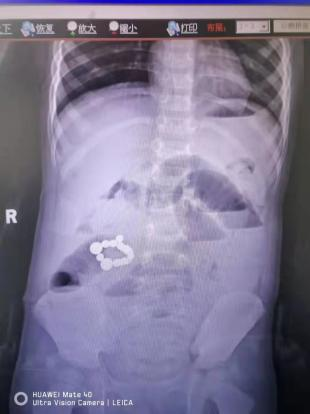

近日,一名2岁男童轩轩(化名)因剧烈腹痛、腹胀送入我院治疗,经腹部DR检查,发现右侧中腹区不规则状致密影,疑似吞食了磁力珠。磁力珠不同于其他珠类,一旦吃2颗以上,很难排出,且会在不同的肠管里吸附在一起,挂到肠壁上,造成肠穿孔。